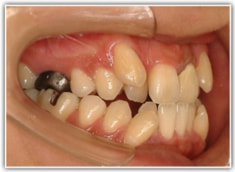

治療後(2年3ヶ月後)

舌位、気道、咽頭扁桃、口蓋扁桃、良好なEラインとプロファイルが得られております。

歯根のパラレリング(平行性)が獲得されております。

下顎8番は、両側抜歯済みです。